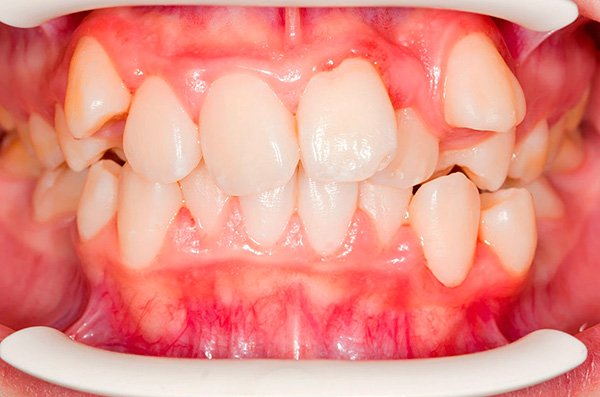

- Dentes super completos - na maioria dos casos, causam problemas de oclusão (aglomeração, diastema, ou seja, o espaço entre os incisivos centrais, bem como a inclinação e rotação dos dentes na arcada dentária). Dentes extragrandes às vezes podem ser detectados acidentalmente após um raio-x. Na dentição, os dentes supranumerários geralmente apresentam uma forma anormal e são quase sempre removidos.

A foto abaixo mostra um exemplo da presença de um dente na mandíbula: